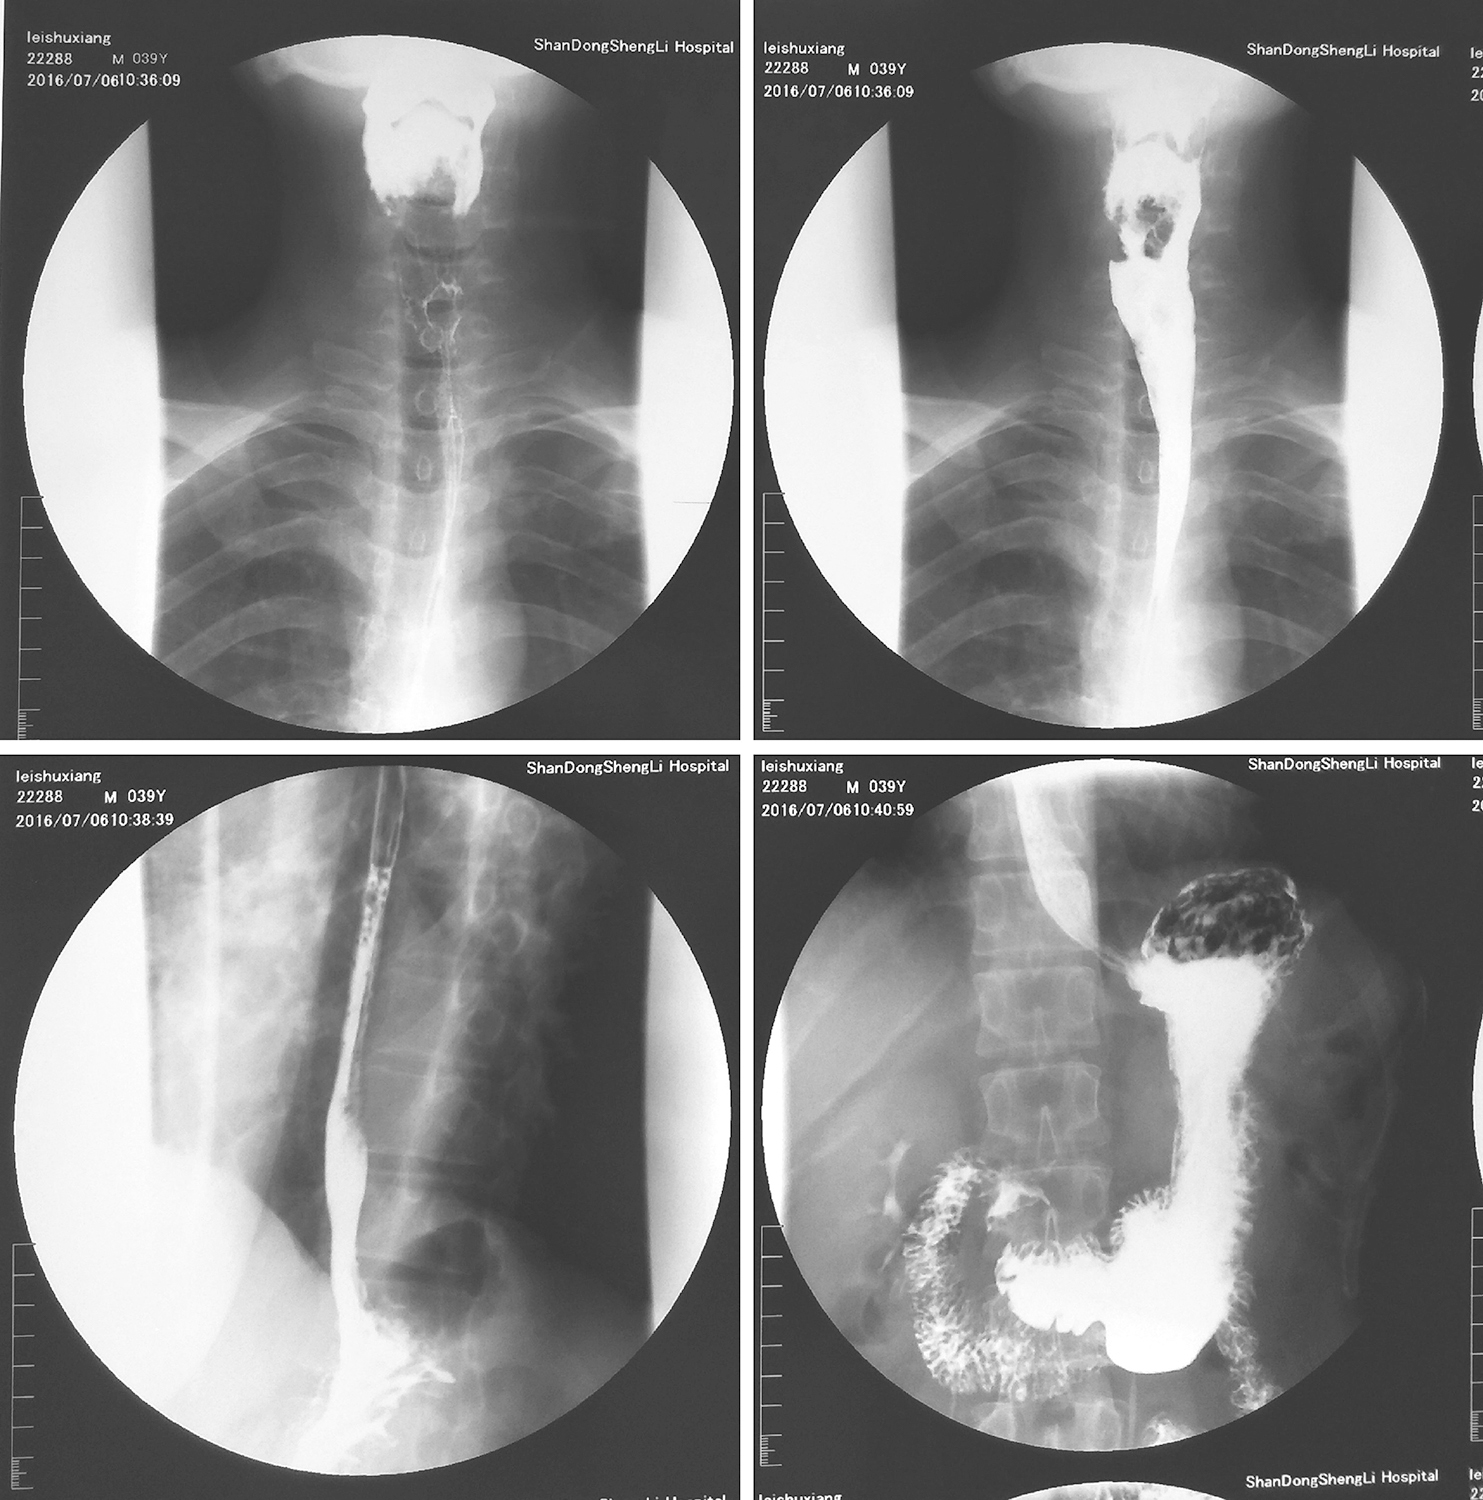

6.2016年7月10日上消化道钡餐透视

下咽部充盈缺损,考虑下咽肿瘤占位(图3)。

图3上消化道钡餐示下咽部充盈缺损